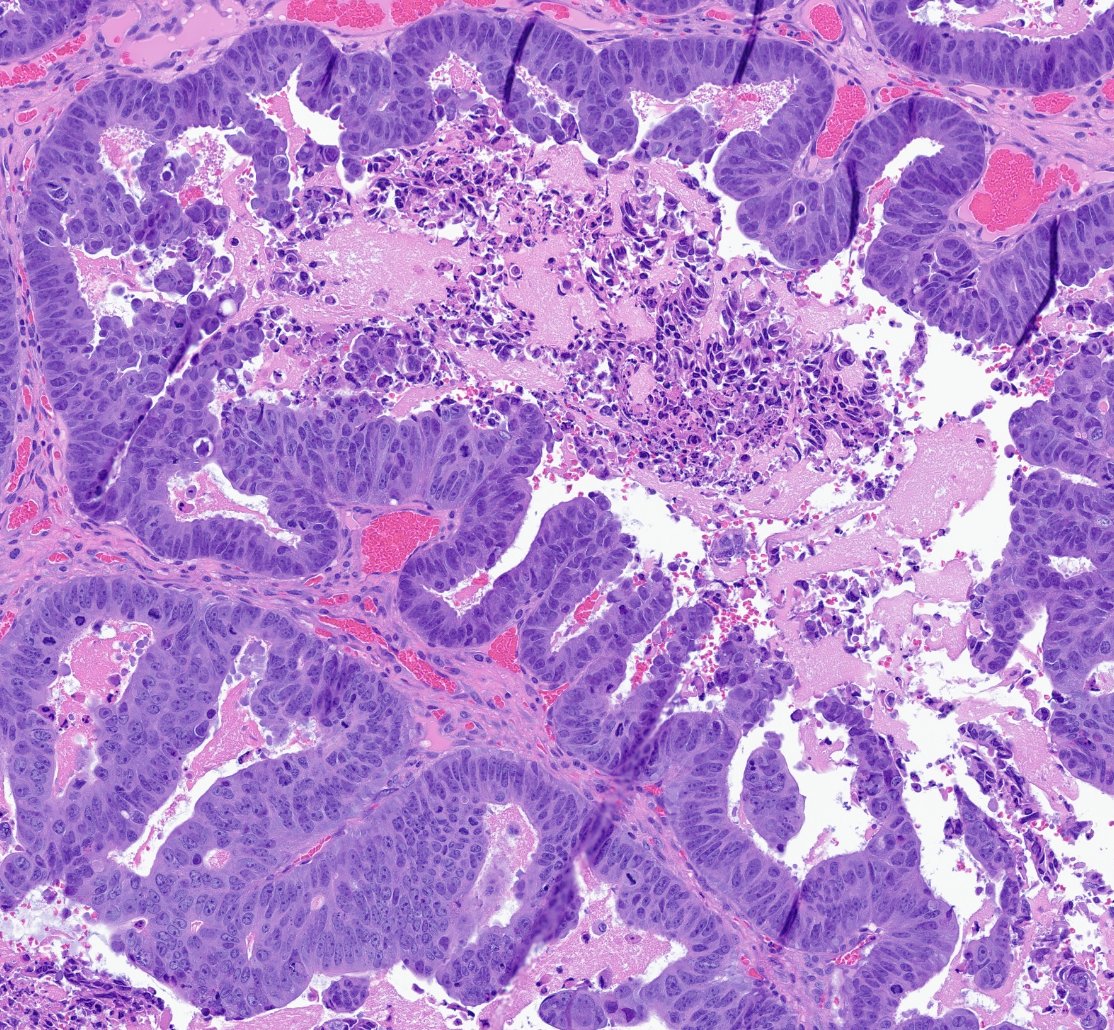

You don't even need immunostains to tell where this brain tumor originally came from. (Reach into the BOWELS of your knowledge base to come up with the answer.) #pathology #neuropath #pathtwitter